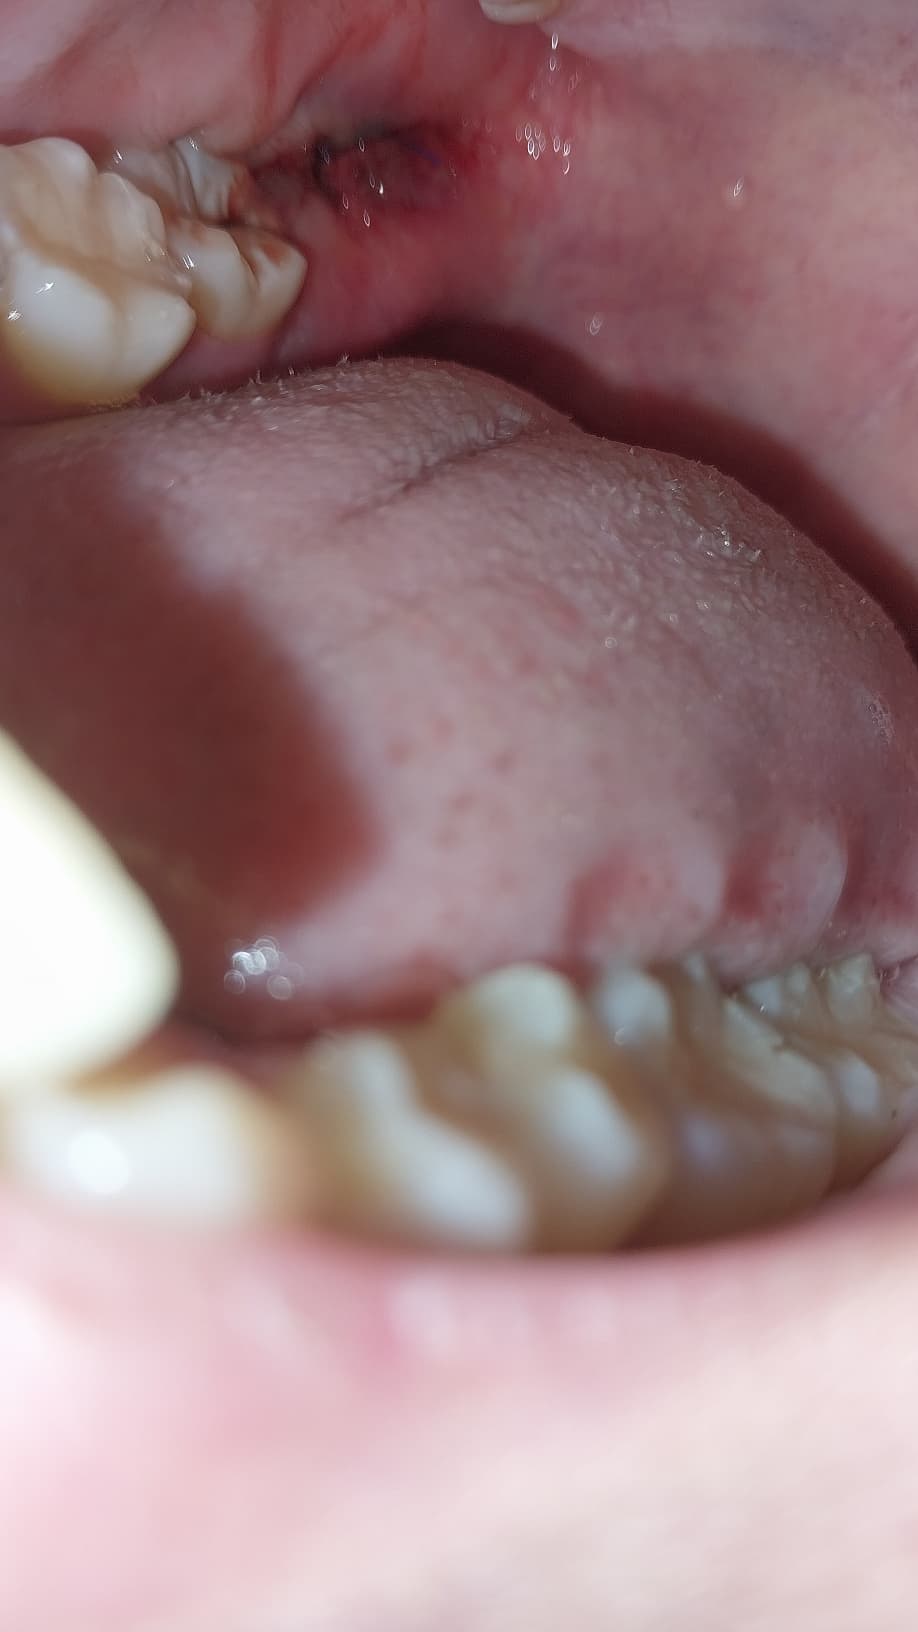

어제 오후 2시에 수평매복사랑니 발치 하고 하루 지났습니다.

어제랑 다르게 발치한 부위가 검붉게 변하고 마치 피멍든것처럼 바뀌었는데 이거 괜찮은건가요?

실제로 거울보니 엄지손가락 한 마디 정도의 크기의 부위가 붉어져 있습니다

피가 났기 때문에 피멍이 든 것 처럼 보일 수 있습니다. 현재는 염증 등의 문제는 보이지 않습니다.